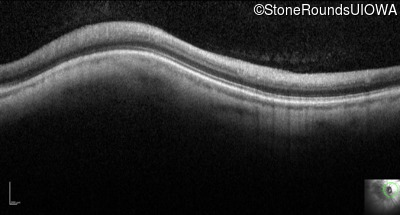

Infrared Fundus Photograph - Right - 20/100

Exemplar